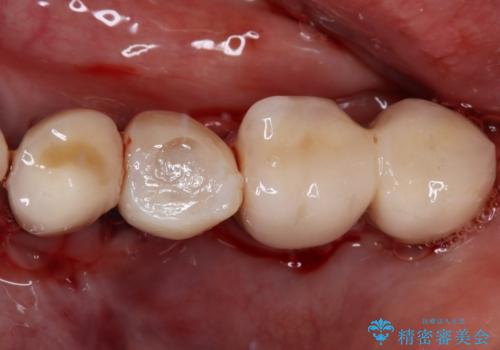

インプラント埋入時に植立具合の安定性を測定したところ、十分な数値が得られたため、速やかに仮歯を装着して咬合回復をさせることができました。

抜歯を含めた外科処置を1回に抑えることができ、あっという間に治療を終えることができました。